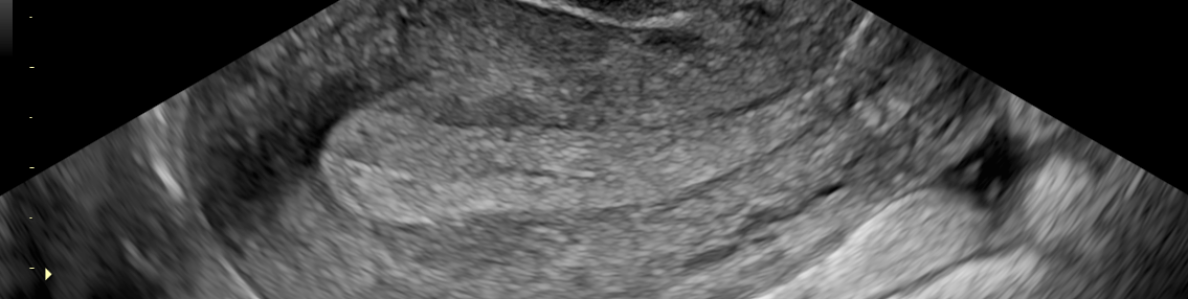

El «Centro Ixchéel en Atención en Salud Reproductiva®» cuenta con alrededor de 80 metros cuadrados de área física y la suficiente tecnología de vanguardia para brindar atención Integral en Salud Reproductiva en Ginecología y Obstetricia, Patología Cervical; Papanicolau, Colposcopia, Criocirugía, Electrocirugía, Tratamiento Moderno e Integral del Papiloma Virus, Vacunas Contra el Papilomavirus, Tratamiento de Infecciones Vaginales, Pruebas de Bienestar Fetal; Perfil Biofísico, -NST-, Ultrasonido Ginecológico y Obstétrico, con las más modernas instalaciones y equipo para brindar atención de calidad y soluciones integrales para la salud, llevando el proceso de atención a otro nivel y accesible económicamente a toda la población.